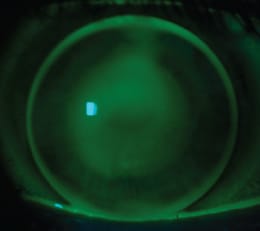

This 24-year-old man had moderate bilateral keratoconus with intracorneal implants in the left eye. He presented with an extrusion of the nasal segment, and he had only the temporal segment (Figure 1). The patient had been fitted with several brands of GP lenses for keratoconus, but he developed lens intolerance. He was then fitted with a piggyback system, but in less than 6 months, he showed signs of conjunctival hyperemia and corneal hypoxia.

Figure 1. Note the elevation around the inferior extremity of the temporal segment; the photo is turned to the right for better visualization.

We initially fit the right eye with a GP Ultracone lens (Ultra-lentes, Brazil) designed for keratoconus. We observed that with this lens design, the elevation caused by the inferior extremity of the corneal ring was high enough that the lens would bear on it and cause corneal staining. To address this, we developed a customized solution using the Ultracone Post-Corneal Ring (PCR) GP lens, also manufactured by Ultralentes. We increased the back optical zone and the sagittal depth so the lens would vault the entire central and paracentral cornea without touch while preventing air bubbles (Figure 2). This multiaspheric design was comfortable enough to help the patient adhere to the adaptation process and succeed with his new lens. Figure 3 shows this patient after 3 months of wearing this lens all day and removing it only to sleep.

Figure 2a. Ultracone PCR Customized fitting.

Figure 2b. Tear film flowing free, no touch.